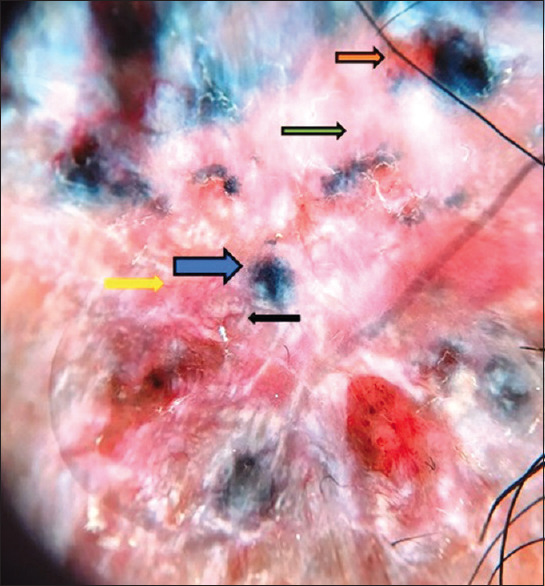

Basal cell carcinoma (BCC) is the most common form of skin cancer, which presents with local invasion, has low metastasizing potential and a cure rate of 100% after surgical excision. BCC commonly involves sun-exposed areas with approximately 80%-85% of BCC located on the head or neck, 15% on the trunk, and <2% in unusual areas such as the abdomen, genitals, perianal skin, lateral edge of the foot, axilla, superior or inferior lip.